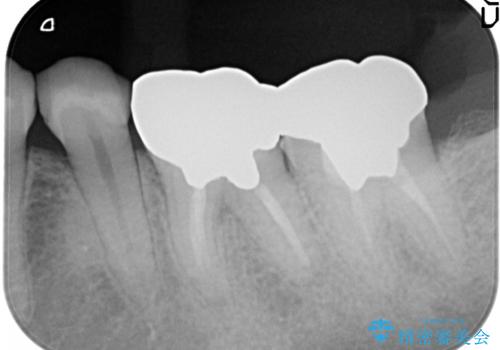

- 金属冠を白くしたいことを主訴に来院されました。

オールセラミッククラウン(st)にて修復しております。

根管治療も合わせて行なっているため、期間がかかっております。